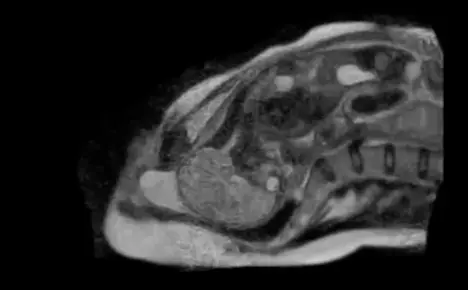

Dr Christian Bamberg, at Berlin’s Charité University Hospital led the project. “It is about understanding the physical mechanism of birth, a dynamic process, with the child performing a complex movement inside what is a very tight space,” he told The Local.

“The baby turns a tight corner in the birth canal and stretches its head and neck as it is born,” he said.

“In the 1950s some researchers took X-rays of births. That of course is obsolete and it would never be carried out today. But that only showed us the bones, none of the musculature, no soft tissues; it did not have any of the dynamism which we see here.

“This is the first time we have a cinematic MRI sequence of the birth of a child. That is something special.”

In an article entitled “Human birth observed in real-time open magnetic resonance imaging,” Bamberg says the MRI machine, which is very noisy, was switched off before the baby’s head emerged, to try to protect his ears from the sound. The article also states that MRI is considered safe to babies and mothers, and is already widely used in pre-natal examinations.

Bamberg said the aim of the study was to help understand abnormal births. “This was a normal, uncomplicated birth. When we understand the normal process we can better see what is going on when things are not progressing so well.”